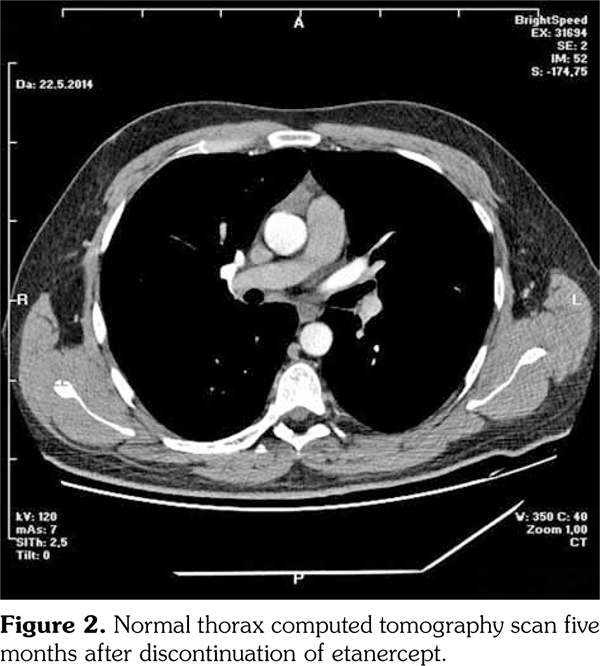

A 29-year-old male patient who had AS for 13 years applied to our rheumatology outpatient clinic for routine yearly control. His AS had been under control with etanercept for 43 months. After the routine follow-up evaluation, a thorax computed tomography scan was performed because of hilar enlargement in the chest X-ray. Multiple lymphadenopathies, the largest one with 2 cm in diameter, were detected in computed tomography scan (Figure 1).